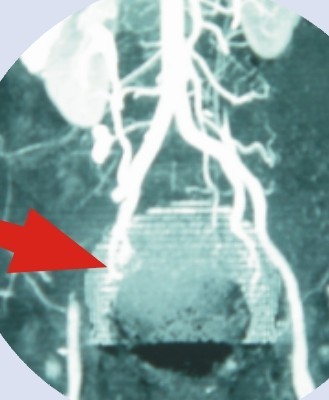

动脉栓塞常高发于哪些部位呢?

根据临床统计,动脉栓塞高发于下肢,最常见的是股动脉,其次是髂动脉和腹主动脉分叉,上肢动脉有3/4发生于肱动脉,另外,腹腔内脏动脉也可能发生,最常见的表现就是肠系膜动脉栓塞引起的小肠坏死。

遇到怀疑肢体动脉栓塞的患者,一般血管外科医生通常会触摸远端的脉搏,如果没有脉搏,要高度怀疑了,常用的辅助检查是彩色超声,能检查到动脉血管是否还有血流,也能看见动脉中的栓子。另外,血管外科医生在治疗中,会采用动脉造影,评估栓塞动脉的部位和范围并同时进行治疗。